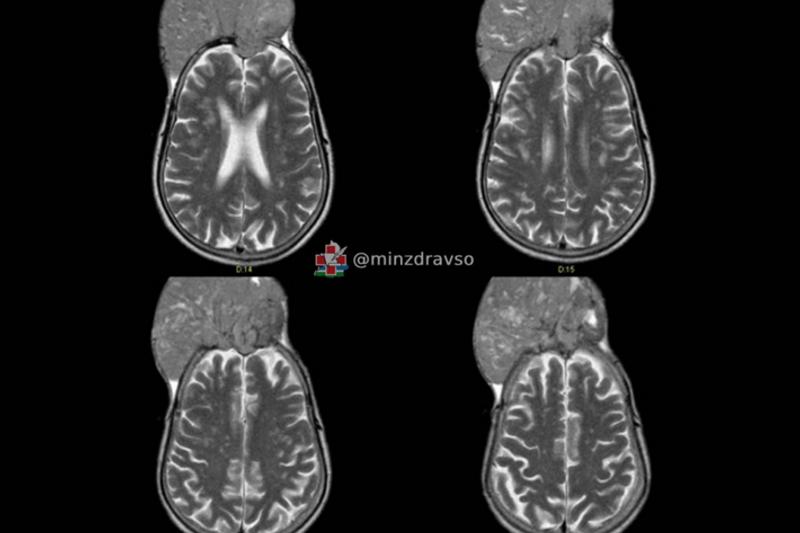

«Житель Краснотурьинска поступил в отделение нейроонкологии, когда опухоль уже проросла кости черепа и распространилась наружу примерно на 10 см. При этом она не вызвала никаких симптомов. На вопрос, почему пациент так долго не обращался к врачам, хотя "вторая голова" росла буквально на глазах, мужчина ответить затруднился. В итоге новообразование достигло размеров примерно 15 на 15 см», — пояснил нейрохирург Свердловского областного онкодиспансера Павел Гвоздев.

Сначала специалисты провели малоинвазивную операцию, чтобы «закупорить» нужные сосуды, от которых была запитана опухоль. Затем новообразование отделили от головного мозга пациента. На всю операцию у врачей ушло семь часов.